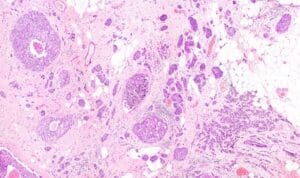

Several prognostic factors indicate the state and progression of breast cancer. Grading of the state of progression and spreading of cancer enables to start the suggested treatment. In solid tumors, like breast cancer, one such prognostic factor is the mitotic figure, i.e. a cell whose chromosomes appear as dark stains. In a histological sample taken from patients, the fraction of breast tissue cells undergoing replication (mitosis) is used to grade the cancer according to scales defined by the oncologist, who in turn suggests the right avenue of treatment.

Abnormal nuclei deformation is the key feature disclosing the mitotic state of a cell. Even in a stained histological sample, in which all nuclei are painted (e.g. blue), extracting the mitotic figure is not a trivial task. Substantial histological training is required to distinguish mitotic from non-mitotic nuclei due to their high similarity. Furthermore, heterogeneity of tissue within the histological sample makes it difficult to assess the actual mitotic figure belonging to the breast tissue.